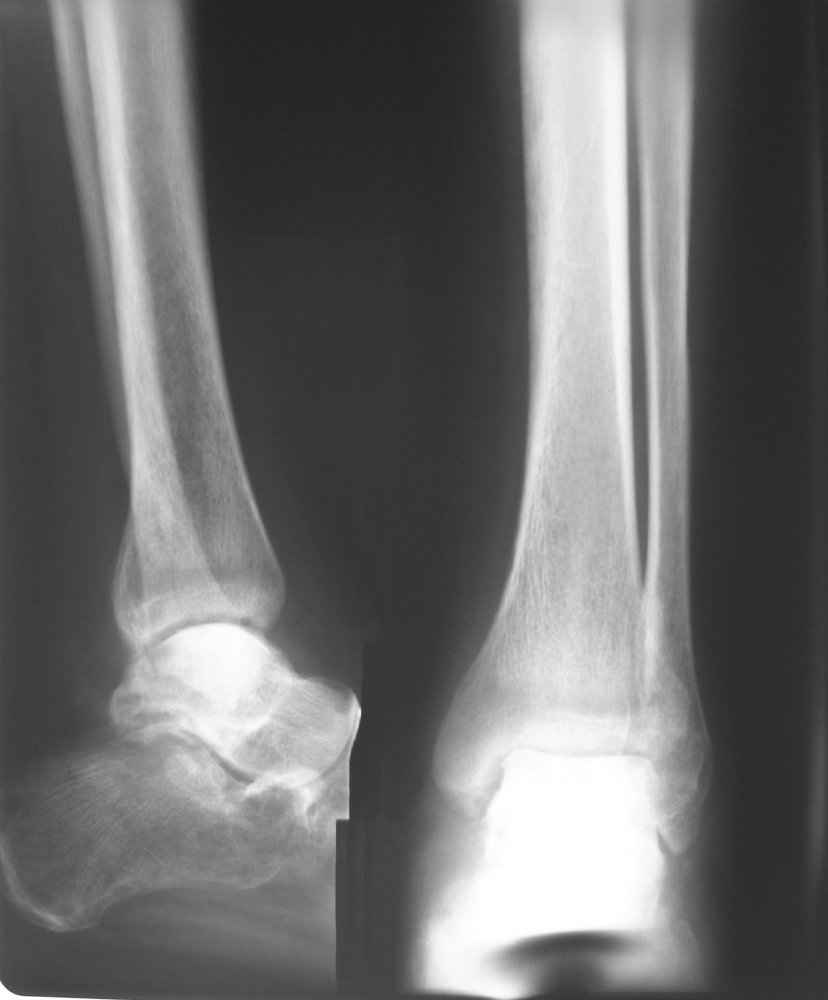

На лечении находится пациент 35 лет. Травма в сентябре 2008 г.- открытый вывих таранной кости

В день травмы ПХО, вправление вывиха, трансартикулярная фиксация. Рана зажила первично. С января нагрузка на конечность. С конца апреля- болевой синдром. На рентгенограммах и КТ признаки ас. некроза таранной кости, артроз подтаранного и голеностопного суставов.

У больного тотальный ас. некрох блока таранной кости, заинтересованы голеностопный и подтараный суставы. Эндопротезирование маловероятно на некротизированную кость. Изолированный подтаранный артродез таран не спасет.При артродезе всю некротизированную кость придется убрать.А далее замещение либо за счет большеберцовой кости, или удлинение на регенерате.